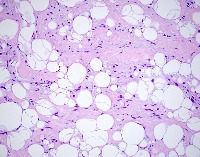

ALipoblastoma

ASpindle Cell Lipoma

Lipoma

Liposarcoma